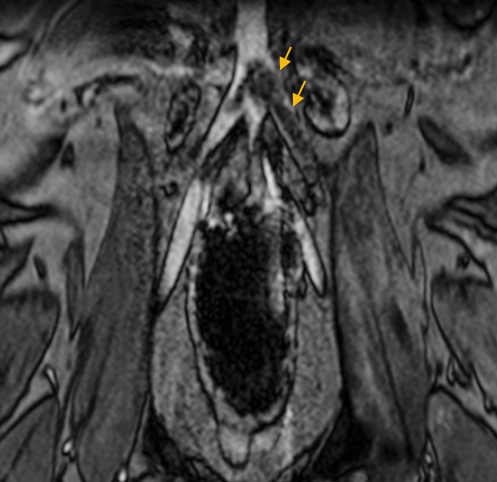

뇌신경·신경근 정밀 평가

신경이 눌리거나 염증이 의심될 때 구조 확인에 도움됩니다.

(참고사진 : 중이·내이 염증으로 8번 뇌신경(청각·균형)에 변화가 보이는 사례)